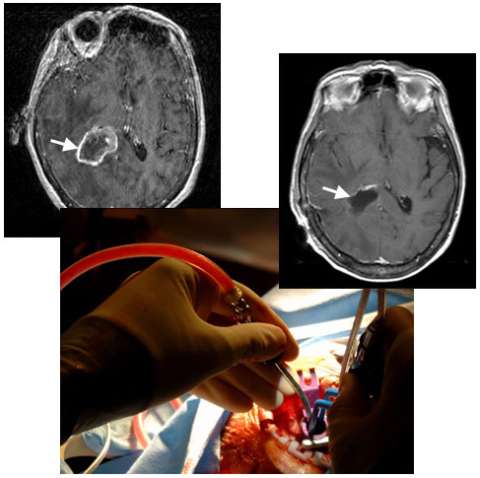

An MRI image (left) shows a metastatic brain tumor from lung cancer in the deep right parietal lobe (arrow). A photograph taken during surgery (center) shows the use a minimally-invasive port, only half an inch in diameter, to gain access so that the neurosurgeon can remove the tumor with minimal injury to the overlying normal brain. An MRI image following surgery (right) shows complete removal of the tumor (arrow) and the hardly visible surgical tract (below arrow).